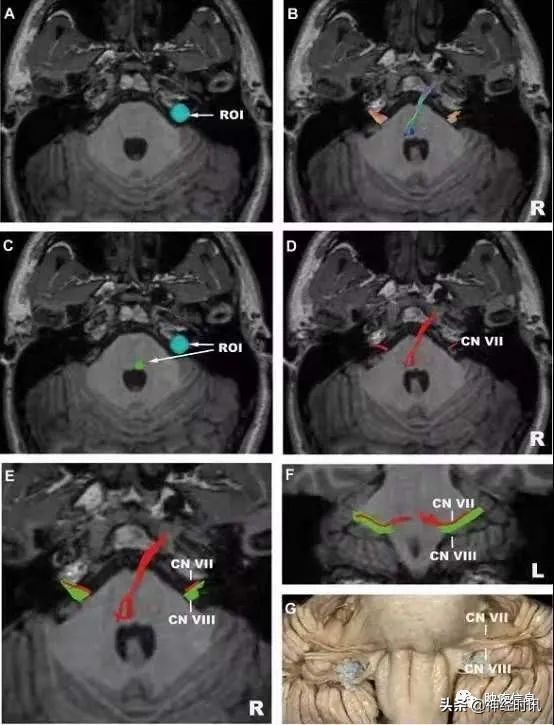

上图 :面、前庭蜗神经。

A,感兴趣区选在内听道处;

B,高分辨率示踪面前庭蜗神经复合体;

C,感兴趣区选在面丘处;

D,高分辨率示踪面神经;

E,高分辨率示踪面神经和前庭蜗神经,红色代表面神经,绿色代表前庭蜗神经;

F,冠状位观察面神经和前庭蜗神经;

G,对应的解剖示意图